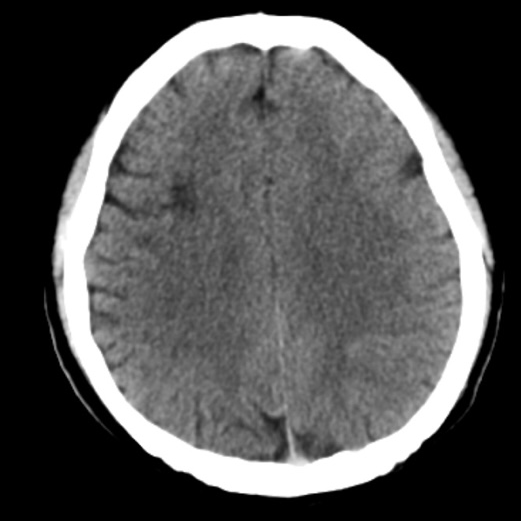

影像学资料

动脉长鞘怎么置入一技之“长”丨经桡及经股困难入路应用赛诺神畅APEX TRA GC™导引导管建立通路病例合集_https://www.jmylbn.com_新闻资讯_第4张

头颅CT: 排除出血